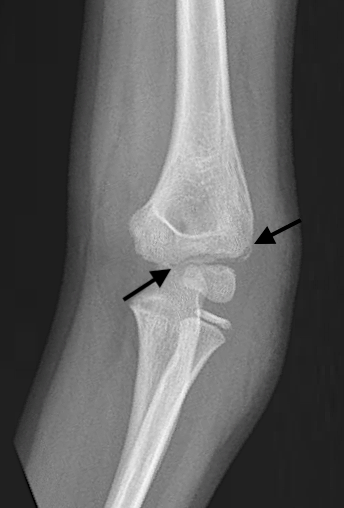

Figure 5B: AP view with markings. This shows two very subtle lucencies (arrows) seen superior and superolateral to the capitellum, consistent with a lateral condyle fracture.